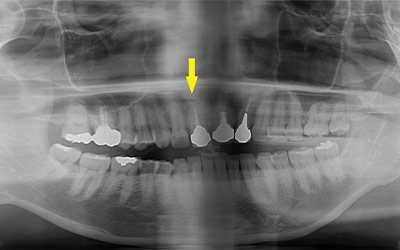

写真は患者様の治療前のレントゲン写真です。右上顎の大臼歯を喪失し、延長ブリッジを装着されていたのですが、支える歯が破折してしまい、抜歯が必要となりました。ここにインプラント治療を行うには、骨が薄くて、困難な状態でした。

CTで見ると、骨が薄いのが良く分かります。黄色の矢印の部分、白く写るのが骨で、矢印のある黒い部分が上顎洞という空洞です。

この空洞部分に、人工骨を入れて、閉鎖しておくと、数か月ほどで骨に置き代わっていき、インプラントを埋入できるだけの骨量になります。サイナスリフトが終了して、数か月経過し、薄かった骨が十分な厚みができたCT画像です。黄色矢印の部分、白く写る骨が増えています。

サイナスリフトを行って、8か月後に、インプラントの埋入手術を行いました。骨が十分にあったので、通常の長さのインプラントが埋入できました。